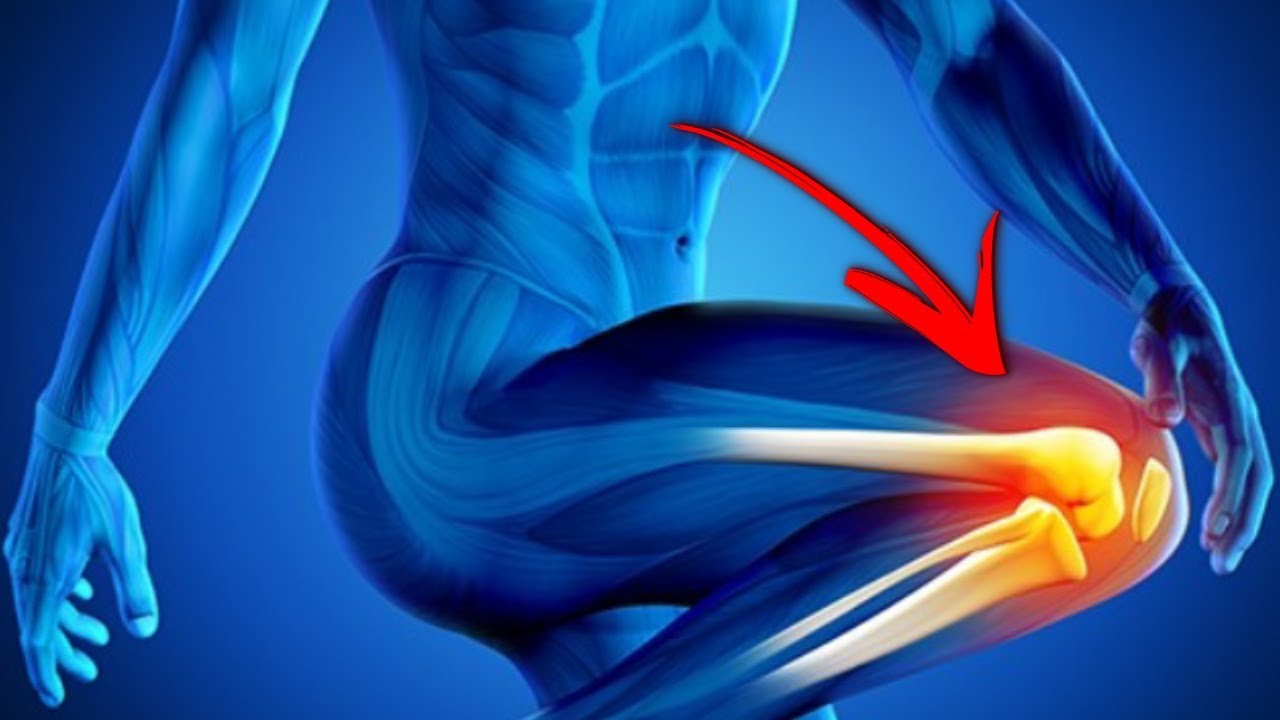

Анатомические рисунки суставов человека